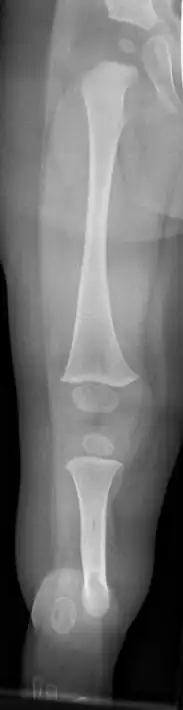

| Fibula hemimelia in patient affecting right side | |

Fibular hemimelia or longitudinal fibular deficiency is "the congenital absence of the fibula and it is the most common congenital absence of long bone of the extremities."[1][2] It is the shortening of the fibula at birth, or the complete lack thereof. Fibular hemimelia often causes severe knee instability due to deficiencies of the ligaments. Severe forms of fibula hemimelia can result in a malformed ankle with limited motion and stability. Fusion or absence of two or more toes are also common.[3] In humans, the disorder can be noted by ultrasound in utero to prepare for amputation after birth or complex bone-lengthening surgery. The amputation usually occurs at six months with removal of portions of the legs to prepare them for prosthetic use. The other treatments, which include repeated corrective osteotomies and leg-lengthening surgery (Ilizarov apparatus), are costly and associated with residual deformity.[4]